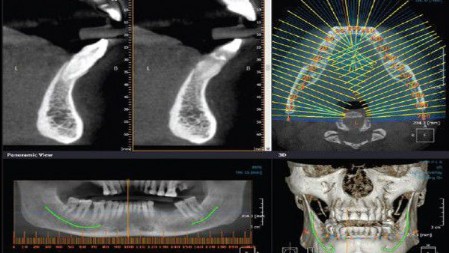

Quando si utilizza ?

- per fini diagnostici e preparatori di interventi di chirurgia implantare. Nel caso in cui la CBCT riveli una scarsa quantità o qualità di osso, prima di procedere all’inserimento degli impianti dentali, che non avrebbero adeguato supporto e sarebbero destinati al fallimento, il medico può decidere per un’operazione di chirurgia pre-implantare ovvero, procedere con il rialzo del seno mascellare (sinus lift) o con innesti di osso autologo o sintetico.

- avendo come caratteristica principale, un’elevata definizione delle immagini, consente lo studio e la diagnosi di patologie quali la sinusite mascellare, le fistole, di processi infiammatori periradicolari (attorno alla radice del dente, come il granuloma e l’ascesso dentale);

- in endodonzia per lo studio dell’anatomia radicolare;

- nelle anomalie della dentizione come: sovraffollamento dentale, denti inclusi, disodontiasi (difficoltà di eruzione di alcuni elementi dentari, dovuta a mancanza di spazio o all’ orientamento scorretto del dente)